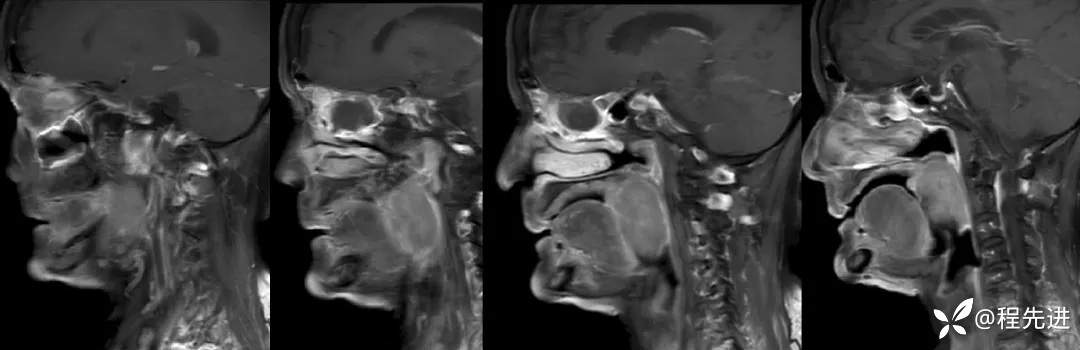

【面颈】特别精彩病例|老年人,反复咽痛1月余,咽部占位期待您的精彩解读!

患者性别:女

患者年龄:78岁

简要病史:反复咽痛1月余

辅助检查:电子鼻咽喉镜:1.咽部新生物性质待定:Ca?淋巴瘤?其他?2.慢性喉炎;3.鼻咽炎

MRI平扫+增强:

T1:

T2: